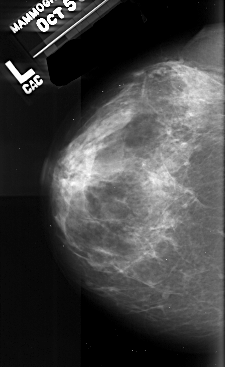

A_1029_1.LEFT_CC

LEFT_CC LINES 5131 PIXELS_PER_LINE 3151 BITS_PER_PIXEL 16 RESOLUTION 42 NON_OVERLAY